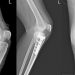

آشنائی با انواع پیچ و پلاک ارتوپدی